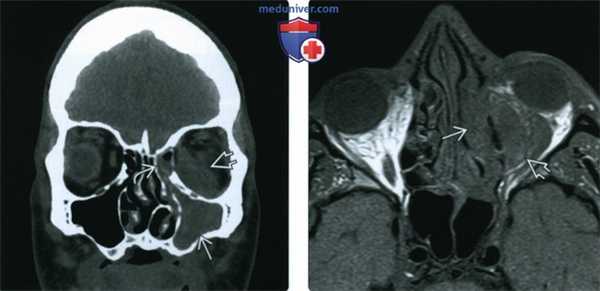

(Слева) При аксиальной КТ без КУ у пациента с диабетом определяется относительно легкое поражение слизистой оболочки правой верхнечелюстной пазухи. Обращает на себя внимание замещение предчелюстной и ретроантральной жировой клетчатки инфильтративным мягкотканным компонентом (подтвержденный ОИГРС, Mucor). Определяется незначительное нарушение целостности костей задней стенки верхнечелюстной пазухи.

(Справа) При аксиальной MPA (ТОР) после экзентерации правой орбиты определяется неравномерное сегментарное сужение просвета кавернозного сегмента правой внутренней сонной артерии вследствие ОИГРС (Mucor).